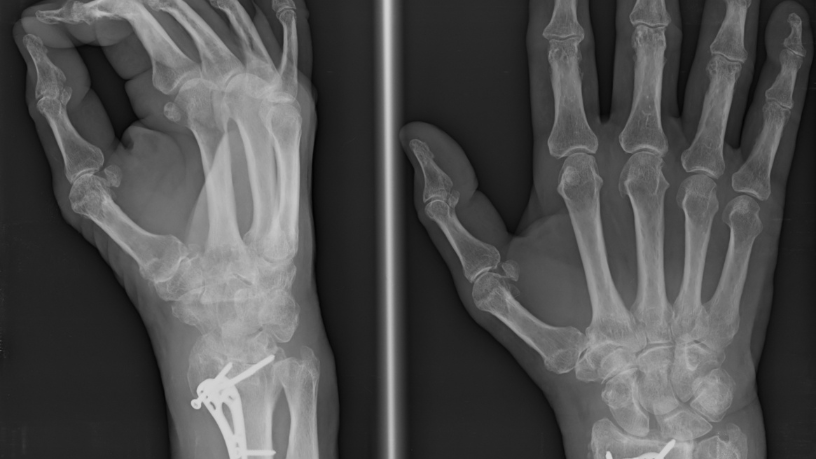

O impacto do especialista em radiologia torácica e telerradiologia Gustavo Khattar de Godoy na radiologia brasileira é notável. Sua expertise em áreas como ressonância magnética e tomografia computadorizada cardiovascular tem sido essencial para o diagnóstico preciso de doenças cardíacas e pulmonares, condições que representam um grande desafio de saúde pública no Brasil.